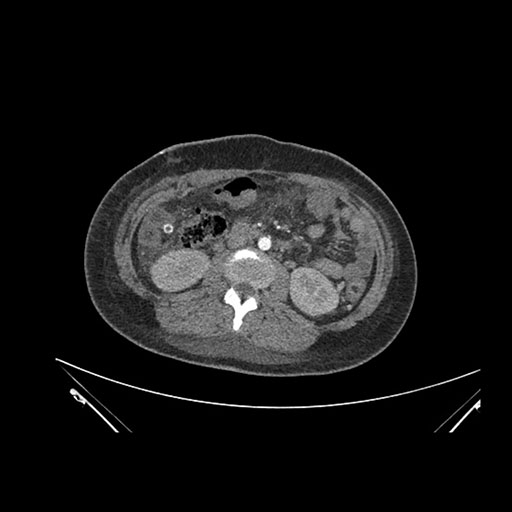

Imaging Analysis

Look through the patient's CT scan to identify any areas of concern for the necessary procedure.

Axial Arterial

Based on initial findings, which issue(s) would you be most concerned about?